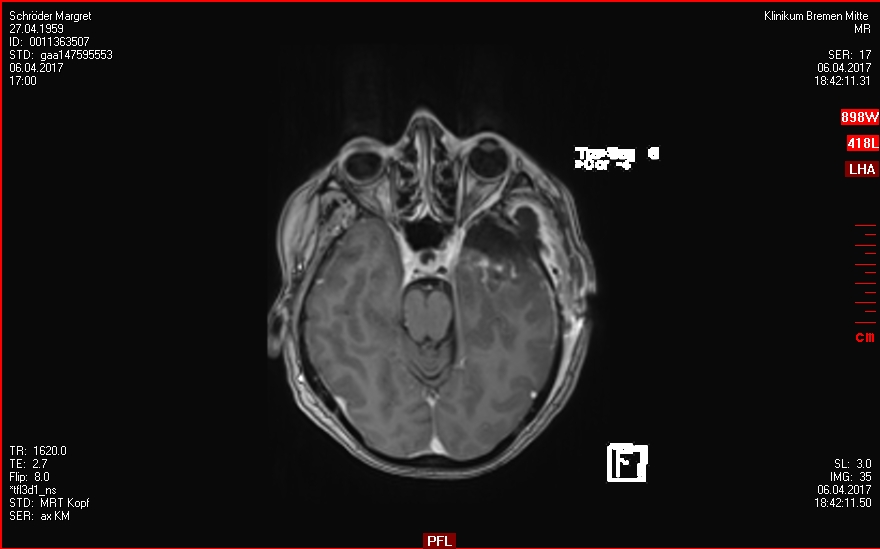

30.03.2017

OP - Krankenhaus Bremen-Mitte

Neurochirugie

Resektion des Keilbeinflügelmeningeoms links